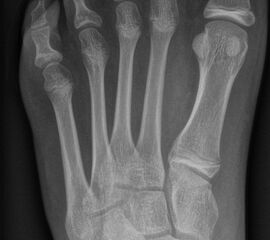

Abb. 2 a-c: offene Wachstumsfugen MT I Basis und Zehen (a), teilweise geöffnete Wachstumsfugen (b) und geschlossene Wachstumsfugen (c).

Die erforderlichen Osteotomien sind daher dem Fugenverlauf anzupassen, diese sind unbedingt zu respektieren. Wird eine Wachstumsfuge versehentlich mit der Fräse verletzt, kann durch partiellen oder kompletten Fugenverschluss ein Fehlwachstum provoziert werden. Achsabweichungen oder ein Wachstumstopp der betroffenen Region können die Folge sein. Offene Wachstumsfugen begrenzen die Osteotomieausrichtung besonders im Bereich des dorsalen Calcaneus, der Metatarsale I Basis und der IV. oder V. Zehe im End- und Mittelglied.